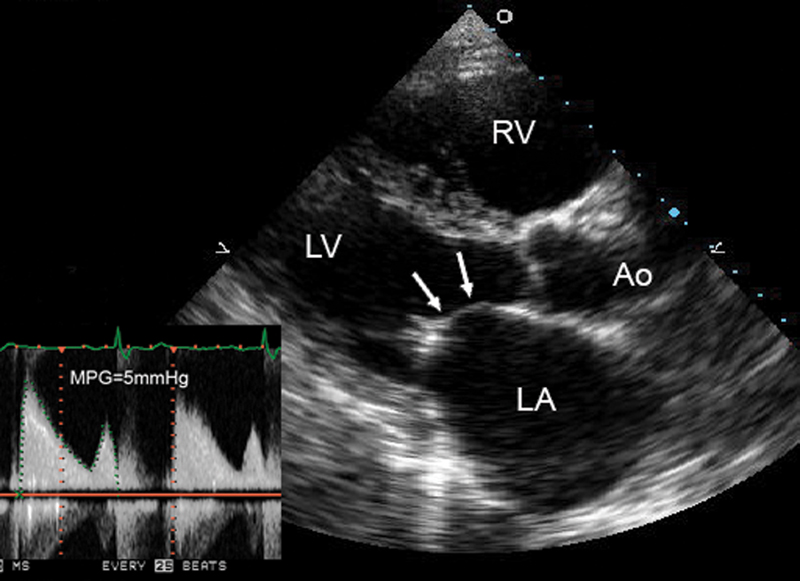

فحوصات تشخيصية لبعض امراض القلب والشرايين التاجية